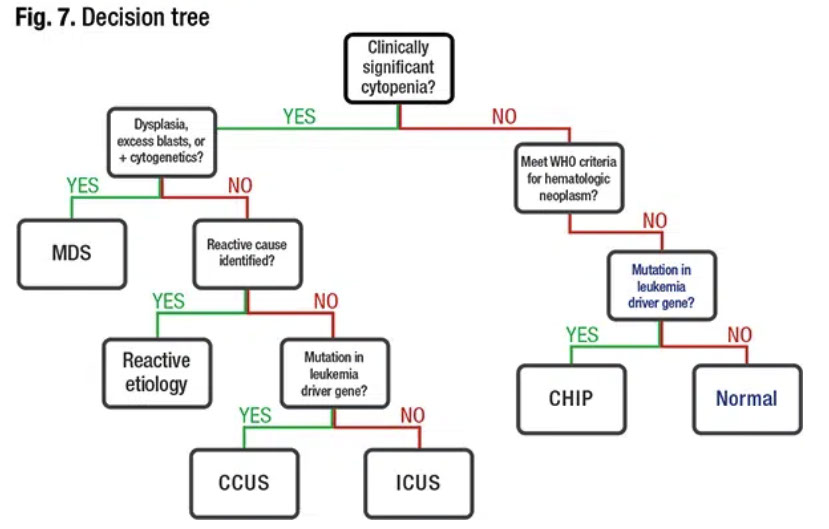

Figure 6. Hematopathology alphabet soup: a quick comparison. With CHIP, ICUS, CCUS, and MDS. From Albert C. Integrating NGS into the cytopenia workup. CAP Today; May 2022.

MDS diagnostic algorithm tree. From Albert C. Integrating NGS into the cytopenia workup. CAP Today; May 2022.